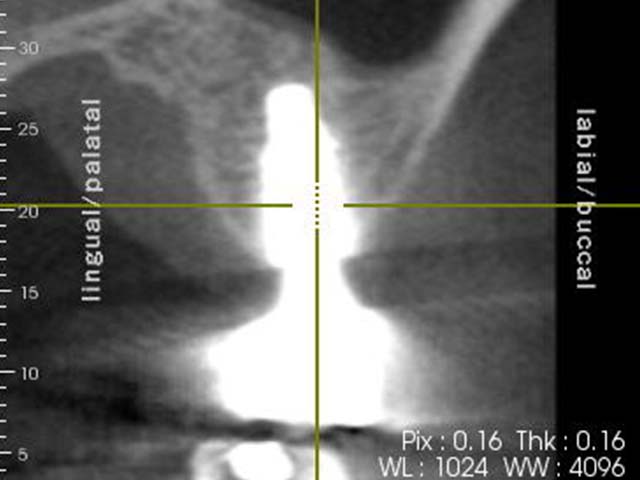

鼻竇增高術(垂直)+植牙 首頁 案例分享 人工植牙 鼻竇增高術(垂直)+植牙 鼻竇增高術(垂直)+植牙 術前評估 PRF(使用法國離心機,萃取出有益於傷口癒合的血小板,並加以濃縮) 鼻竇增高術 從植牙傷口置入萃取的PRF,將鼻竇往上抬升,再植入骨粉,以利植牙。 電腦斷層—術前,術中,假牙完成